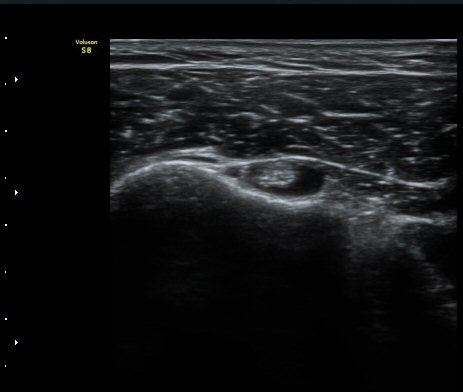

¿Í ¼Ò°áÀý »óºÎ(±×¸² 4)¿¡¼­ ƯÀÌ ¼Ò°ßÀ» º¸ÀÌÁö ¾Ê´Â´Ù.